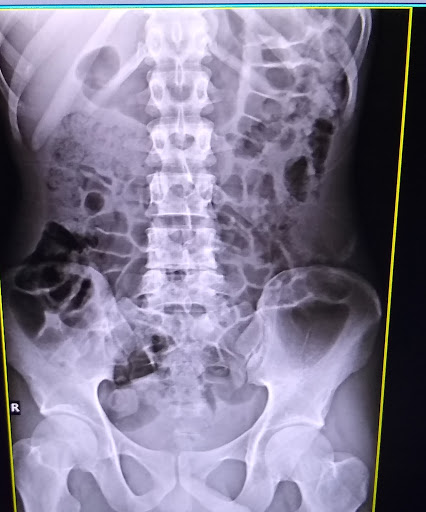

Paraparesis with L4,L5infective spondylodiscitis with left psoas abscess with ring enhancing lesions in right and left cerebral hemispheres with multiple nodules in pulmonary apices suggesting of Disseminated tuberculosis with healing ulcer in right gluteal region secondary to drained gluteal abscess with pyocele left side operated ( 10 days back).

Pott Disease (Tuberculous Spondylitis)

2)Cold abscess formation down along the psoas muscle, Petit's triangle, Scarpa's triangle, or the gluteal region is common.The patient in this case has gluteal abscess.

4)As the Patient has got Paraparesis with L4,L5infective spondylodiscitis with left psoas abscess I strongly think this case to be Tuberculous Spondylitis